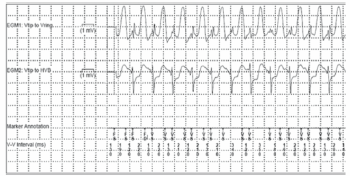

A interrogação por telemetria do dispositivo revelou eventos de alta frequência ventricular com o seguinte padrão no eletrograma intracavitário

Enunciado 2057783-1